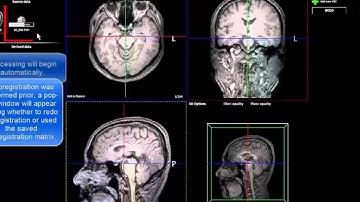

nordicBrainEx v2.1 How to perform dti analysis